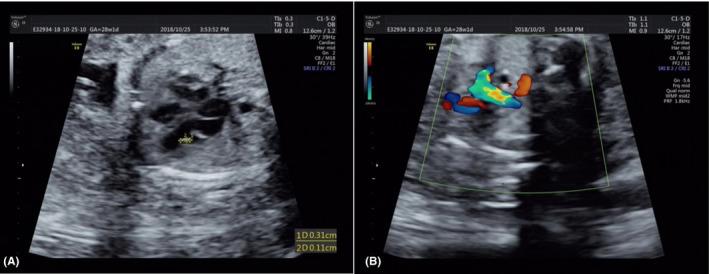

The case was a fetus at 28 weeks of gestation. The risk of Down syndrome from second-trimester screening was 1/140. Prenatal ultrasound and amniocentesis were performed, and chromosomal microarray analysis (CMA) was used for genetic analysis.

RESULTS

The fetus had abnormal clinical features, including intracardiac echogenic focus in the left ventricle, an aberrant right subclavian artery, and growth delay. The fetal chromosomal karyotype was 46,XX,15q?,12q?,21pstk+, and CMA revealed a 10.163 Mb duplication at 15q24.3-q25.3. The couple chose to terminate the pregnancy after careful consideration.